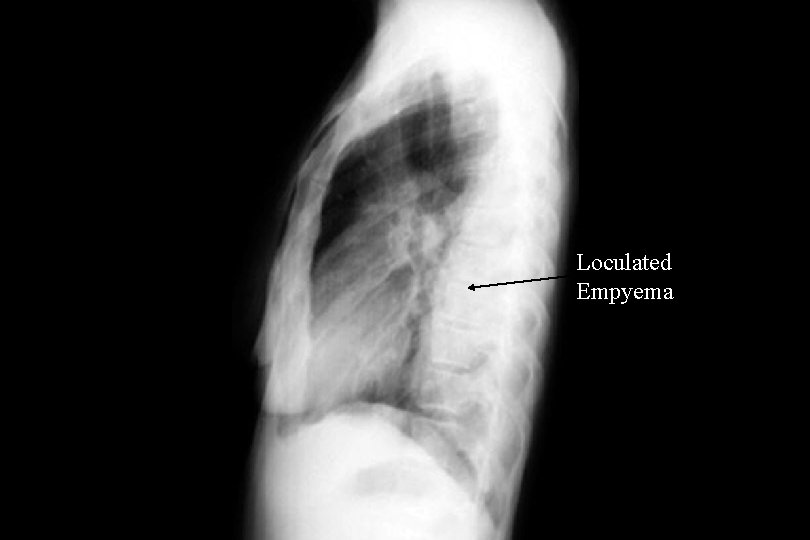

Loculated empyema Sub pulmonic effusion

Loculated Empyema